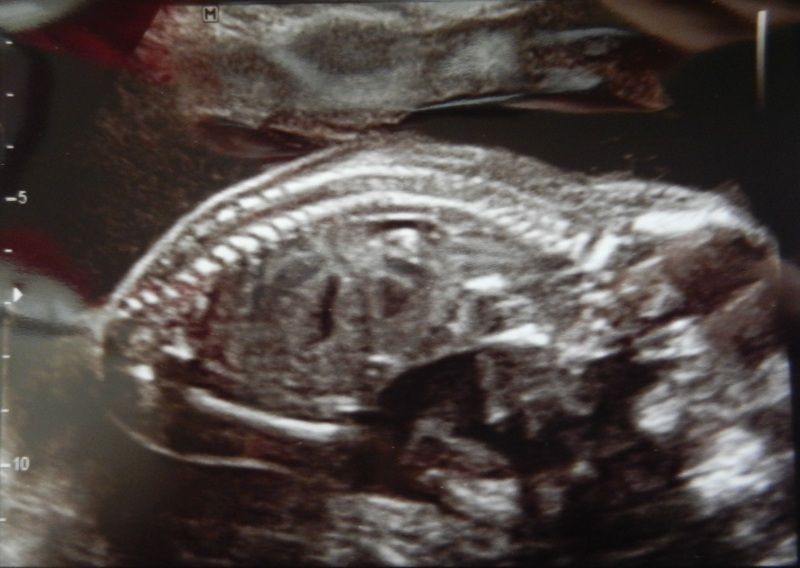

Zo lag ie even later, face down, lijkt nu al op mama met de rare lenige ligposities: